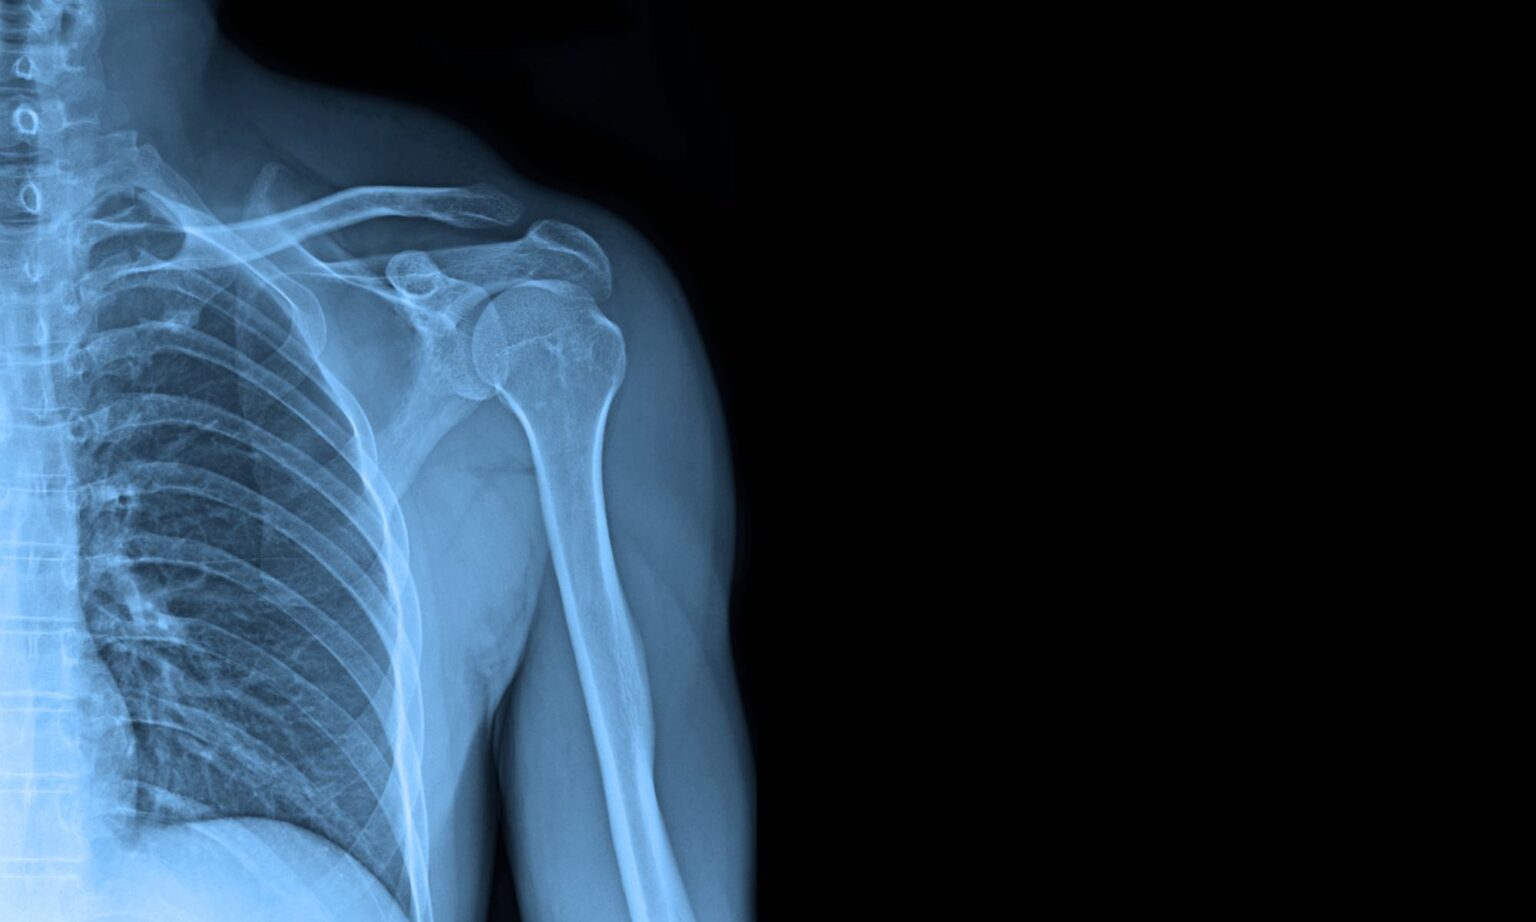

Can An X Ray Show Rotator Cuff Tear . rotator cuff tears are the most common cause of shoulder pain and result in loss of strength and loss of stability of the shoulder. It allows us to understand the tear’s pattern, including. rotator cuff tear arthropathy is a spectrum of degenerative disease that develops due to a rotator cuff deficient shoulder. The term encompasses both rotator. Ultrasounds can be used to monitor the muscle and tendons while you move your arm.

ROTATOR CUFF TEAR, XRAY Stock Photo Alamy Can An X Ray Show Rotator Cuff Tear rotator cuff tears are the most common cause of shoulder pain and result in loss of strength and loss of stability of the shoulder. It allows us to understand the tear’s pattern, including. The term encompasses both rotator. Ultrasounds can be used to monitor the muscle and tendons while you move your arm. rotator cuff tear arthropathy is. Can An X Ray Show Rotator Cuff Tear.